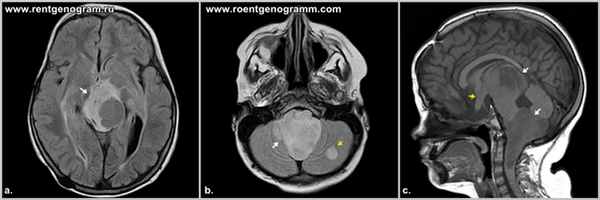

Пилоцитарная (пилоидная) астроцитома — опухоль детского возраста, характеризуется относительно «отграниченным» характером роста (в отличие от диффузных астроцитом) и имеет характерные особенности локализации, морфологии, генетического профиля и клинического течения. Относится к самой низкой (1-й степени злокачественности по классификации ВОЗ для опухолей ЦНС) и имеет наиболее благоприятный прогноз. Чаще встречается в возрасте до 20 лет. Наиболее частая локализация — мозжечок, зрительные пути, ствол мозга. Клиническая картина характеризуется очень медленным нарастанием как фокальной (в зависимости от локализации опухоли), так и общемозговой симптоматики с хорошей адаптацией организма. Особенно характерно медленное нарастание окклюзионной гидроцефалии при опухолях мозжечка и ствола мозга. Диагностика. Опухоль имеет характерную КТ и МРТ семиотику, что позволяет вместе с клинической картиной поставить диагноз до операции. Стандартом предоперационного обследования таких больных является проведение МРТ с контрастным усилением. Лечение хирургическое, цель операции — «тотальное удаление» опухоли, что часто невозможно из-за локализации (ствол мозга, гипоталамус). Прогноз. Выживаемость больных часто составляет более 10–15 лет, в связи с чем точных значений по выживаемости не существует из-за трудностей с анализом столь длительного катамнеза. Примечание. Среди пилоидных астроцитом (чаще гипоталамических) имеется небольшая подгруппа опухолей с выраженным локально «инвазивным ростом» и склонностью к метастазированию по субарахноидальным пространствам.